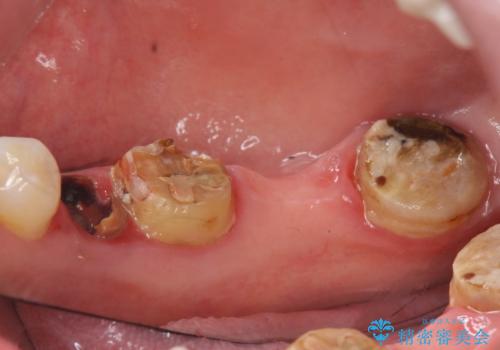

- 右下の奥歯の被せ物が外れてしまったので診て欲しいといらっしゃった方の症例です。

右下7は欠損しており、右下5は保存不可能だったため、インプラントによる欠損補綴を行いました。